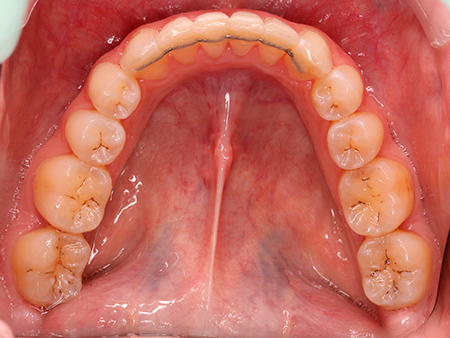

Ana vino a la clínica porque no estaba contenta con su sonrisa. Ella había llevado brackets anteriormente pero, al no haber usado la retención de manera adecuada, los dientes habían vuelto a su posición inicial.

Después de analizar su caso, nuestro equipo de ortodoncistas le aconsejó abordar un tratamiento de ortodoncia. Su objetivo era corregir el apiñamiento y la sobremordida que presentaba tanto en la arcada superior como en la inferior.

Tras un procedimiento de ortodoncia con alineadores transparentes Invisalign de 21 meses de duración, Ana ya disfruta de una sonrisa estética y funcional.